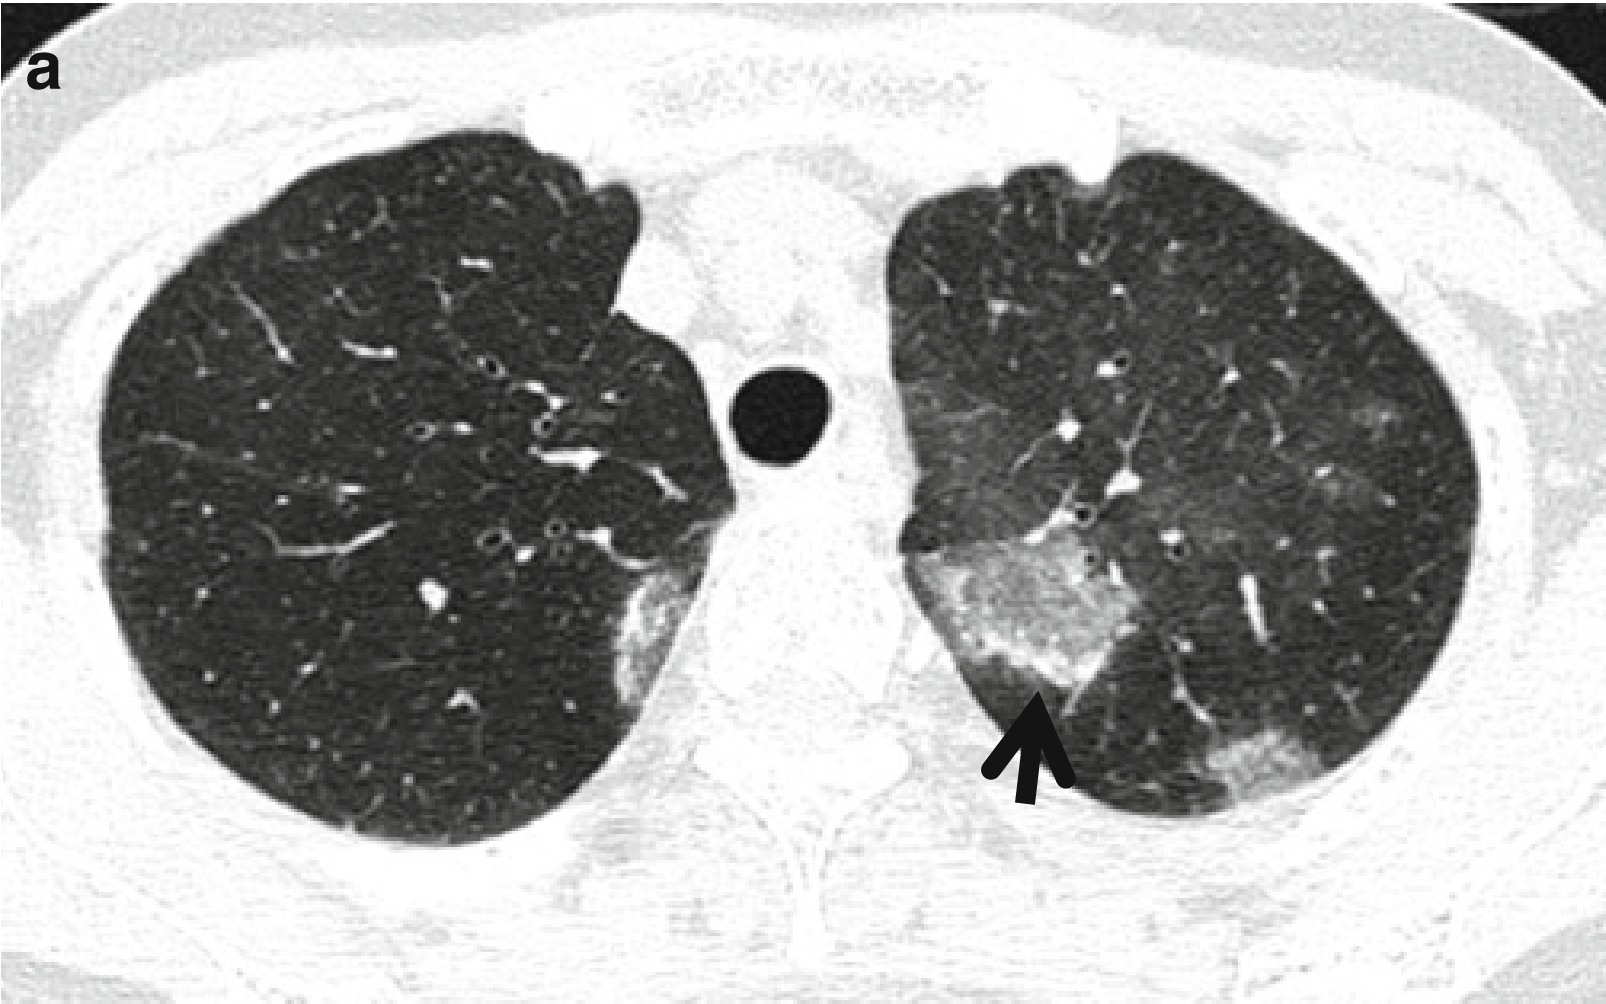

图2 表现为反晕征的隐源性机化性肺炎。

女,58岁。

(a,b)薄层CT扫描(层厚=2.5mm)肺窗分别于肝上下腔静脉水平(a)和右膈顶水平(b)示双肺多发磨玻璃密度病灶,并可见反晕征(箭头所示)。

CT表现:典型CT表现为单侧或双侧肺实变影。将近60%病例,实变主要累及胸膜下或支气管周围区域或两者均累及。GGO通常和实变影一并出现。30%~50%的病例可见边界模糊的小结节。通常呈小叶中央性分布。在广泛肺实变患者,可见空气支气管征和牵拉性支气管扩张,并常局限于实变区域。偶尔COP也可表现为大结节或肿块样实变影。约20%的COP患者可见CT反晕征。

CT-病理对照:组织学上,实变区域对应于肺实质纤维化:GGO对应肺泡间隔炎症和少量纤维化;小结节为局限于细支气管周围的局灶性机化性肺炎和(或)成纤维细胞充填细支气管腔;反晕征中央的GGO在组织学上对应肺泡间隔炎症和细胞碎屑;反晕征外围的环形实变影对应肺泡管区域的机化性炎症。